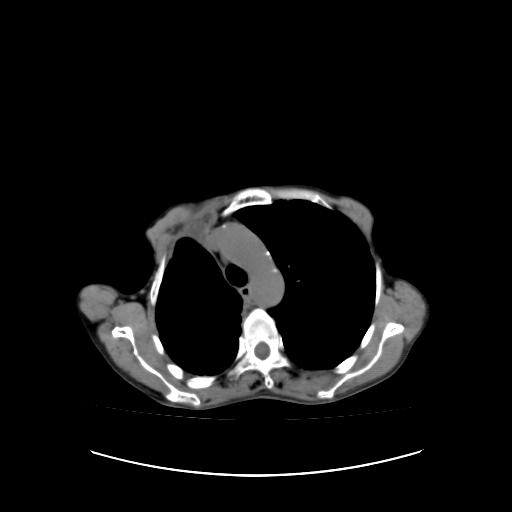

右侧胸膜增厚,局部呈结节状增厚,右侧胸腔少量积液。双肺未见确切肿块影。纵隔未见淋巴结肿大。气管、支气管通畅。考虑右侧胸膜间皮瘤(恶性?)可能性大。不除外癌性胸膜炎。

右侧广泛胸膜增厚,局部呈结节状增厚,右侧胸腔少量积液。双肺未见确切肿块影。纵隔未见淋巴结肿大。气管、支气管通畅。考虑右侧胸膜间皮瘤(恶性?)可能性大。支持!

右侧恶性胸膜间皮瘤可能性大。